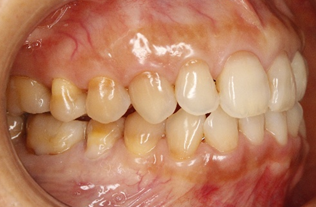

3.上の歯列が右下がりになっている

上の写真の状態では、下顎は左右どちらに動かしやすいと思いますか?

上の歯が下の歯にあまりかぶさっていない左(向かって右側)には動かしやすいですが、右(向かって左側)へは動かしにくいかもしれません。右顎の頭から首にかけての筋肉に負担がかかりやすくなり、左右で筋肉の緊張が異なることから、顔が自然と曲がってしまうことが推測できます。